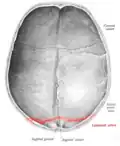

![]() Lambdoid suture (labeled at bottom right) | |

The lambdoid suture is between the paired parietal bones and the occipital bone of the skull. It runs from the asterion on each side.

Lambdoid suture seen from above. -

Lambdoid suture seen from inside. -